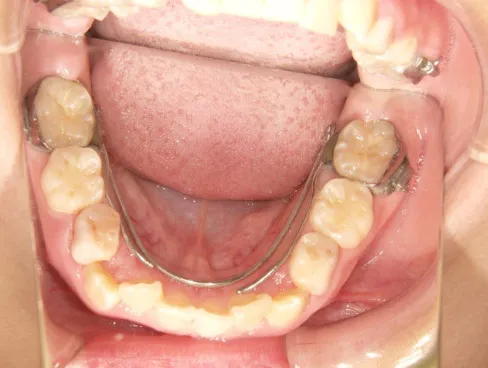

QH

BH

治療中➁拡大・前歯の並替え装置(写真はイメージ)